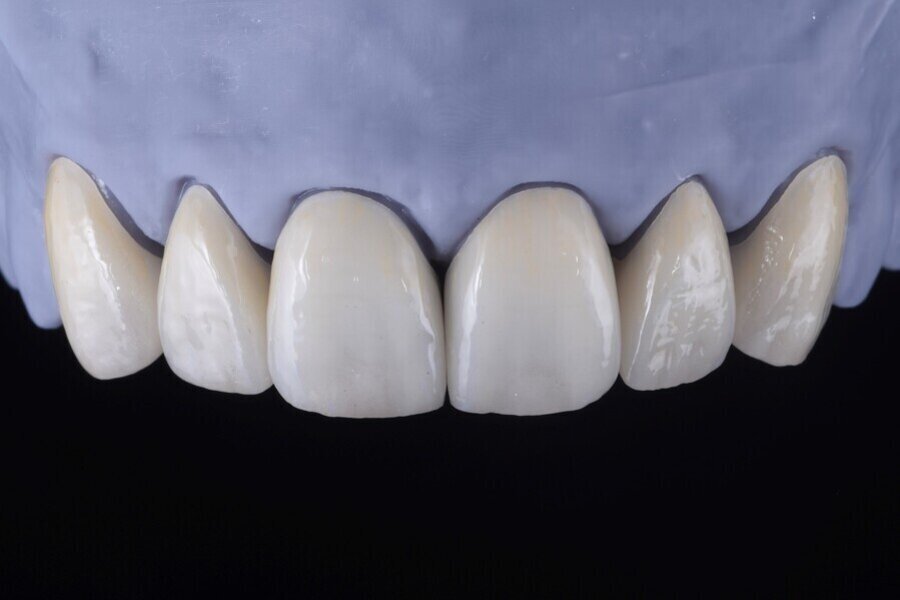

Následně byl zhotoven digitální wax-up ve frontálním úseku horní čelisti, aby bylo možno ověřit estetiku plánované rekonstrukce a vést minimálně invazivní preparaci zubů na základě zhotoveného mock-upu (obr. 8). Finální preparace (obr. 9) se z větší části omezila na interproximální oblasti (obr. 10). Poté byl proveden finální digitální otisk při aplikaci retrakční niti. (obr. 11).

V rámci digitálního designu navržené rekonstrukce byla provedena částečná redukce dolní poloviny bukální plochy plánovaných korunkových náhrad, aby bylo umožněno vrstvení keramiky pro dosažení co nejlepšího estetického výsledku (obr. 12 a 13).

Obr. 13: Konečná rekonstrukce (s prostorem pro frontální stratifikaci).

Obr. 14a, b: Finální náhrady.